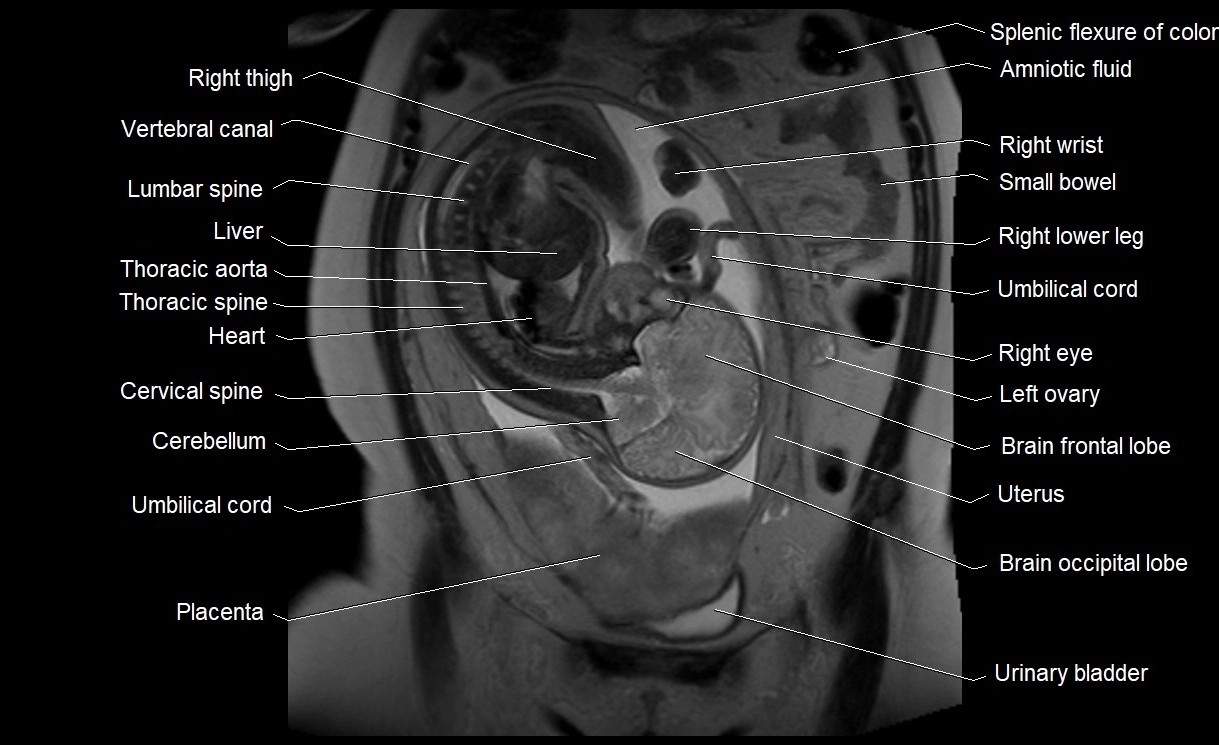

MRI Appearance

T2 HASTE (T2 GRE):

• Amniotic fluid shows very bright hyperintense signal

• Provides natural contrast against fetus and placenta

• Small particles (vernix) may appear as scattered hypointense foci within bright fluid

T1 GRE:

• Amniotic fluid shows low signal intensity (dark)

• Hemorrhage, infection, or proteinaceous content may cause focal or diffuse high signal intensity

MRI image

image